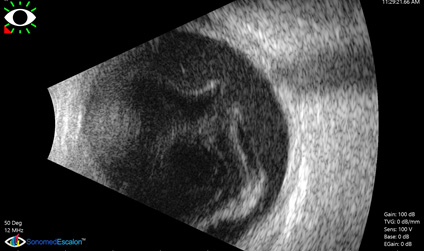

Ecografia ocular modo b

EQUIPOS DE DIAGNÓSTICO OCULAR

Contamos con equipos de última generación y tecnología de punta.